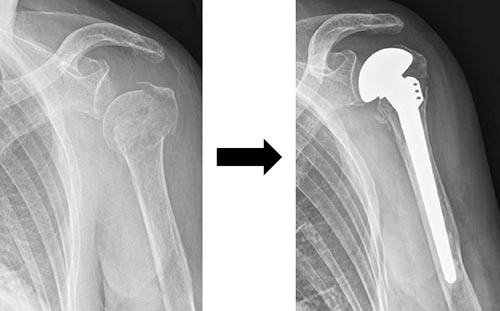

手術方法は、骨接合術は髄内釘固定法(図3)やロッキングプレート固定法(図4)が行われます。脱臼骨折の場合には、人工骨頭置換術が行われる場合もあります(図5)。近年リバース型人工肩関節置換術も用いられるようになり、臨床成績が安定しています(図6)。

図5 肩人工骨頭置換術